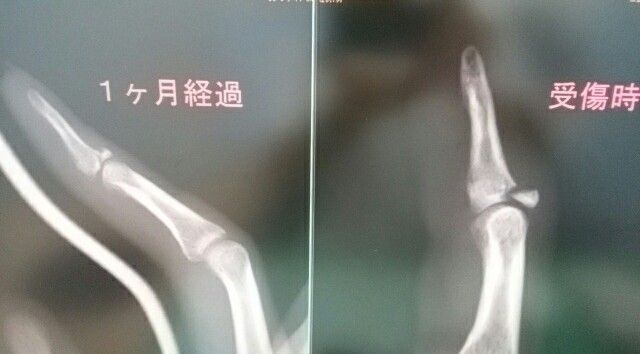

最近、この骨折を良くみかけます

指の中でも、難治性である

マレット骨折

ピンによる手術適応ですが、

保存的に加療すれば、感染のリスク

や痛みもなく、骨癒合を経験します。

拘縮や運動障害も認めないことが

多いですね、